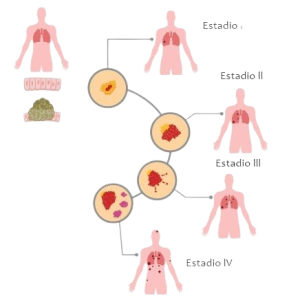

Si el cáncer de pulmón se descubre en una etapa más temprana (cuando es pequeño y antes de que se propague), es más probable que se pueda tratar eficazmente.

Por lo general, los síntomas de cáncer de pulmón no aparecen sino hasta que la enfermedad ya se encuentra en una etapa avanzada. Aun cuando el cáncer de pulmón causa síntomas, muchas personas pueden confundirlos con otros problemas, como una infección o efectos a largo plazo causados por el hábito de fumar. Esto puede retrasar el diagnóstico.

El beneficio principal de las pruebas de detección consiste en una menor probabilidad de morir de cáncer de pulmón, enfermedad que causa muchas muertes en fumadores y ex fumadores. Aun así, resulta importante saber que, como con cualquier tipo de prueba de detección, no toda persona que se haga las pruebas se beneficiará. Las pruebas de detección con LDCT no encontrarán todos los cánceres de pulmón, y no todos los cánceres que se detecten estarán en etapas iniciales.

Las personas que participaron del estudio se sometieron a tres LDCT o tres radiografías de tórax, con un año de diferencia, para detectar áreas anormales en los pulmones que podrían ser cáncer. Después de varios años, el estudio encontró que las personas que se sometieron a una LDCT tuvieron un 20% menos de probabilidad de morir a causa de cáncer de pulmón en comparación con las personas que se sometieron a las radiografías de tórax. En general, también tenían 7% menos de probabilidad de morir (de cualquier causa) en comparación con las personas que se sometieron a las radiografías de tórax.